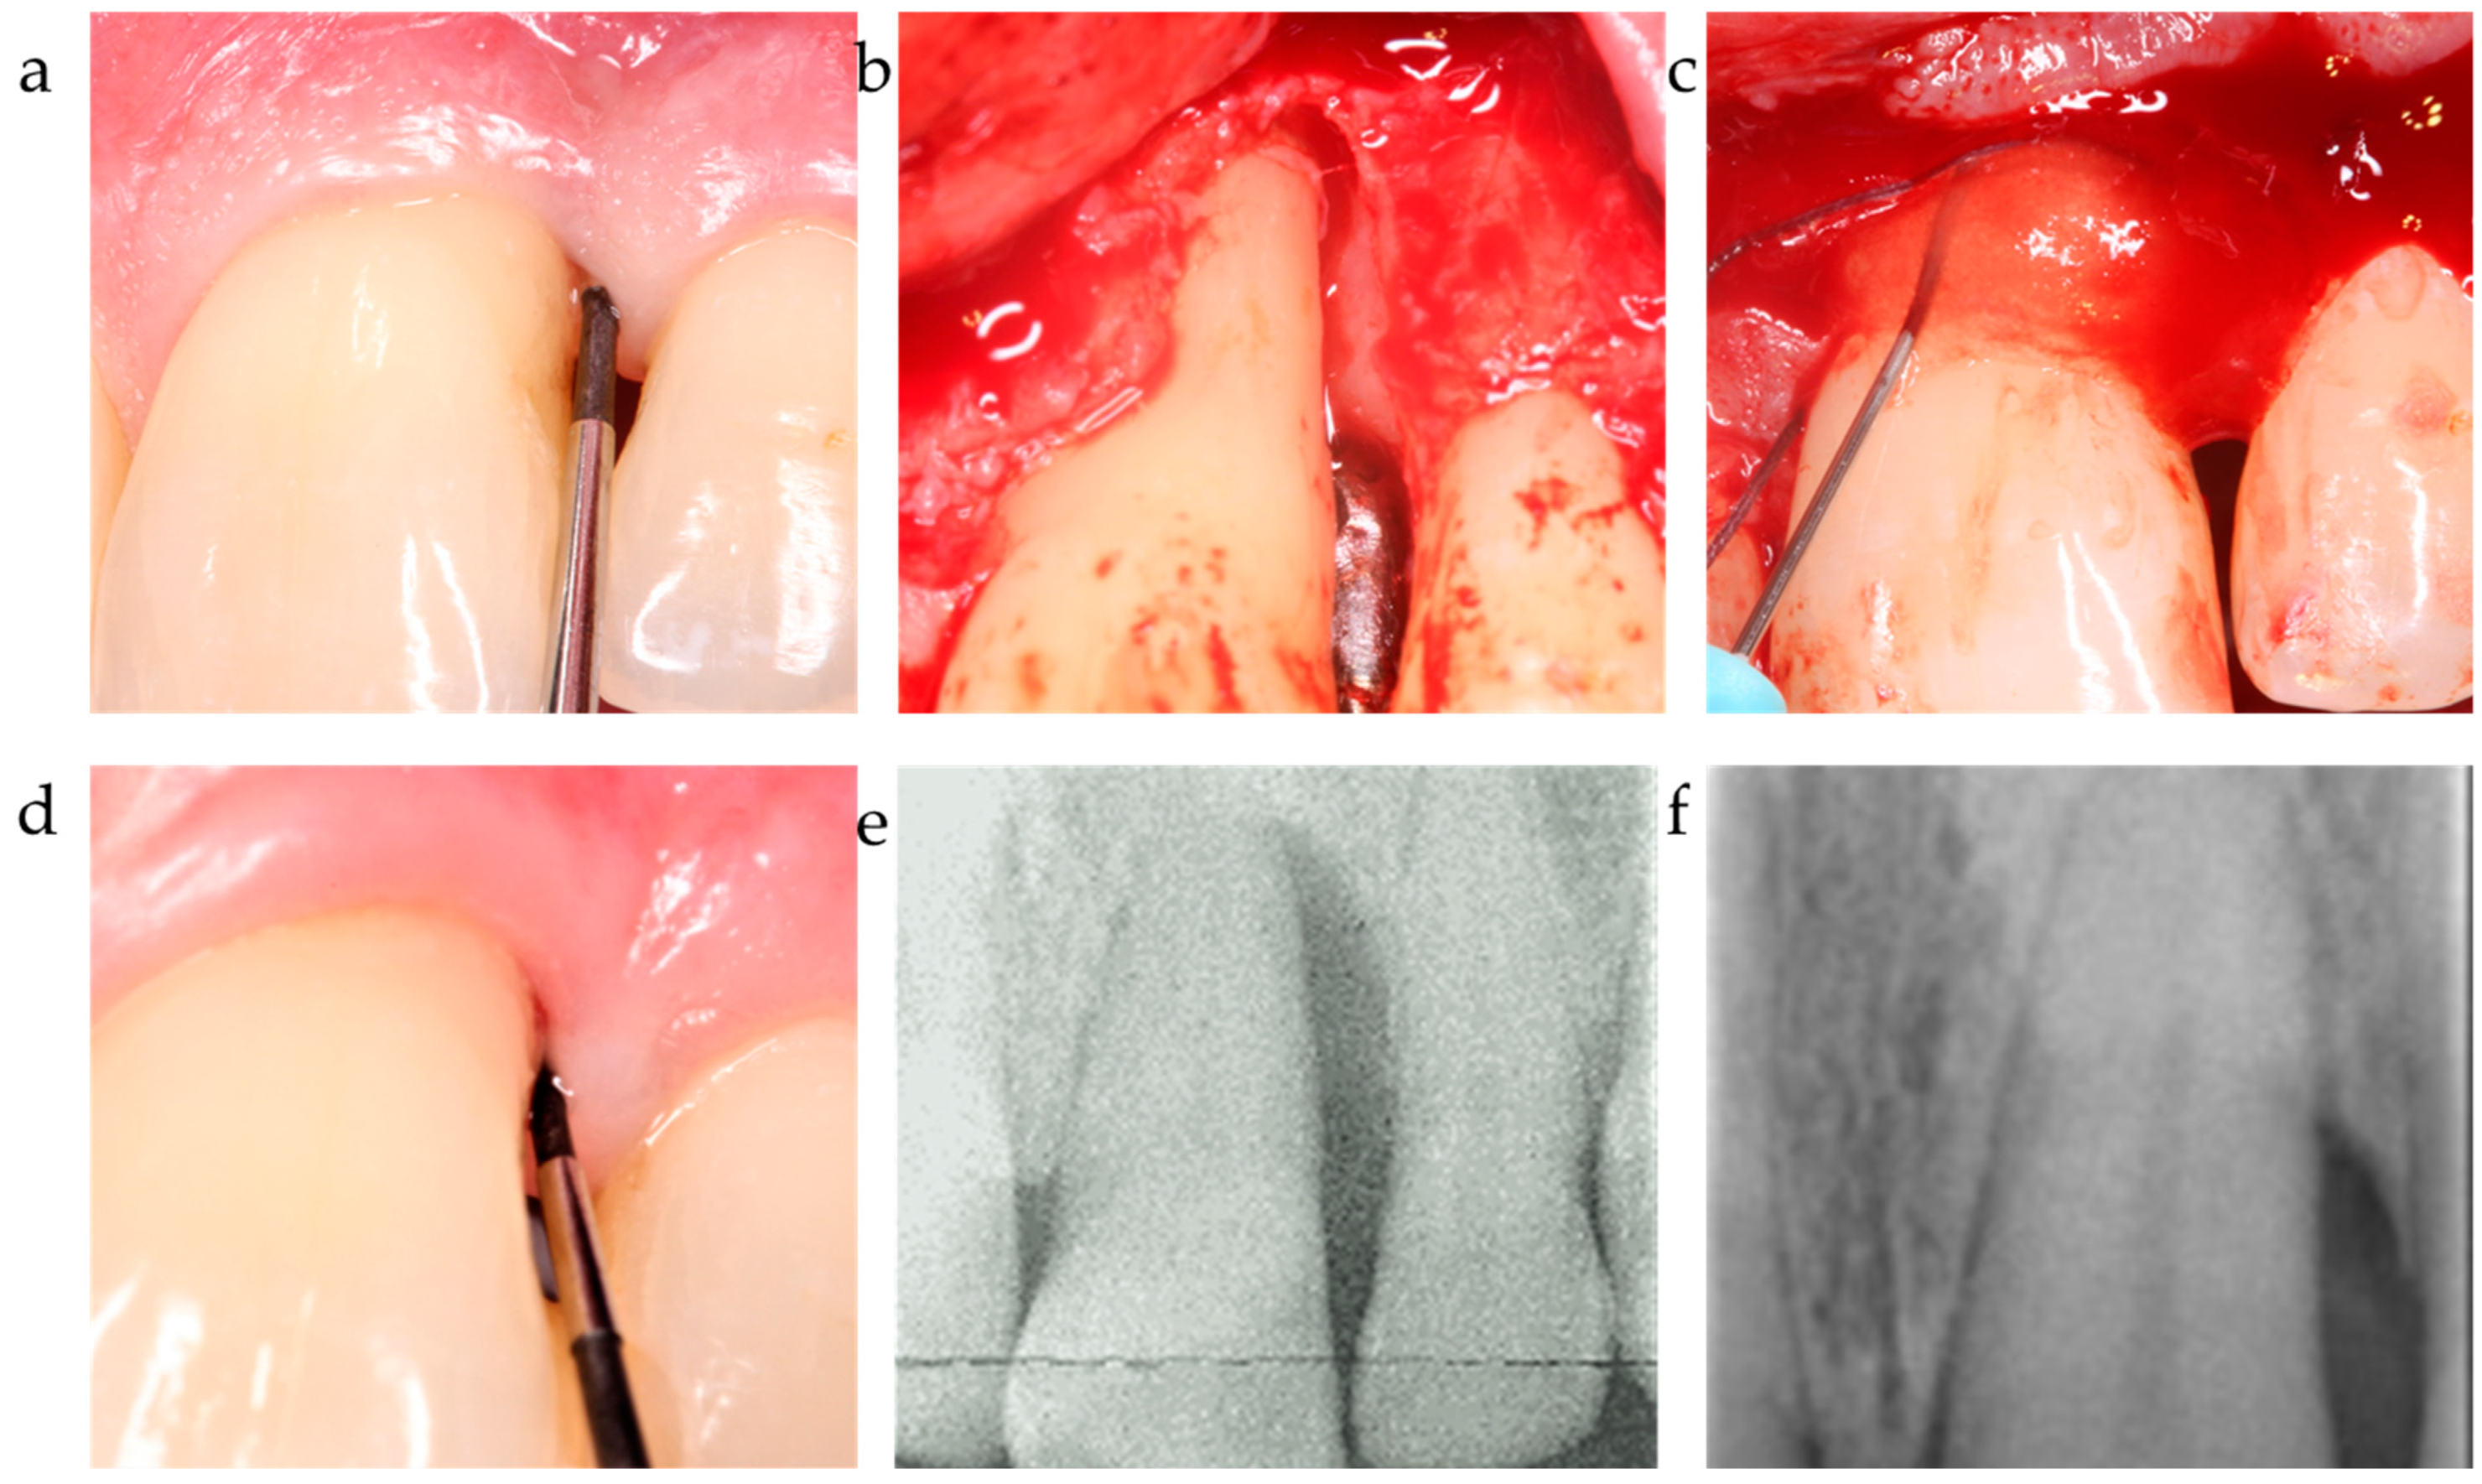

Figure 4.

Center 3 showcase: (a,b) PPD and defect extension; (c,d) defect grafting at surgery as result of barrier placement and xHya application, and clinical outcome at 12-month exam. (e,f) radiographically observed change in bone level around tooth 21 before surgery and 12 months post-op.